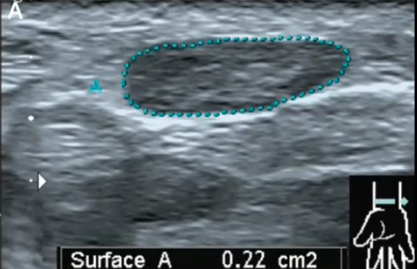

Echographie tendineuse : simple et pourtant ...

COHEN M. , DEMONDION X. , ISCAIN P. - Clinique Juge Marseille & CHRU LILLE

MAP 2013

Musculo-squelettique

US

Tendon

Affections osseuses

Rhumatismes

MAP

1 étapes